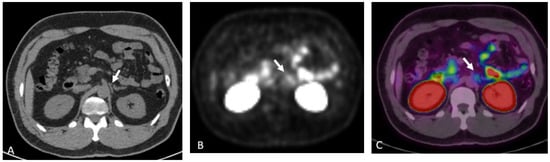

Detection of Loco-Regional Disease and Distant Metastases